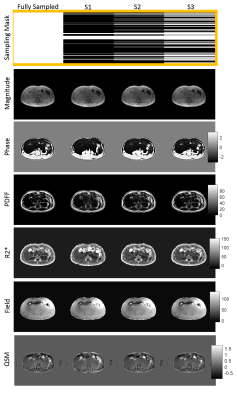

Figure1. Comparison of fully sampled and undersampled (density masks; S1=14%, S2=28.9%, S3=50.7%) reconstruction of magnitude/phase images, water/fat separation results (PDFF(%), R2*(Hz), field (Hz)), and QSM (ppm).